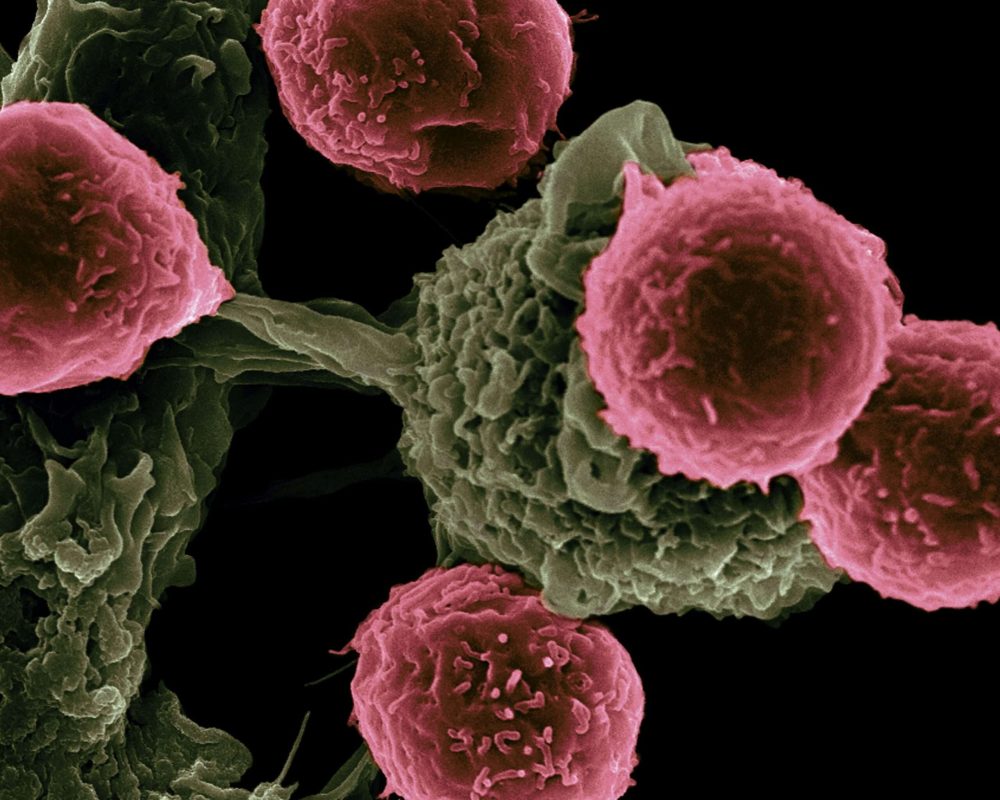

Az egynyári üröm hatásmechanizmusa

Az édes üröm (Artemisia annua) hatóanyagát számos kutatás vizsgálja daganatos sejtek kapcsán. A molekula egyik különlegessége a benne található endoperoxid-híd, amely instabil szerkezet, és a sejtekben jelenlévő kétértékű vasionok hatására felhasadhat. Laboratóriumi vizsgálatokban a kötés felbomlása nagy mennyiségű, rendkívül reaktív szabadgyök képződéséhez vezetett. Ezek a szabadgyökök oxidatív stresszt idéztek elő, ami károsíthatja a sejtek fehérjéit, genetikai állományát és membránszerkezetét. Kutatások szerint a daganatos sejtek különösen érzékenyek erre a folyamatra, mivel anyagcseréjük során több vasat halmoznak fel, mint az egészséges sejtek. Ez a sajátosság magyarázhatja, hogy a növényből kivont hatóanyag egyes vizsgálatokban szelektíven inkább a daganatsejteket érintette, míg az egészségeseket kevésbé. Laboratóriumi és állatkísérletes eredmények arra is utalnak, hogy a hatóanyag előidézheti az apoptózisnak nevezett programozott sejthalál folyamatát. Ez azért különösen fontos, mert a daganatos sejtek gyakran éppen az apoptózis elkerülésével válnak korlátlanul szaporodóvá. Más kutatások szerint a hatóanyaga hatással lehet a sejtciklusra is. Bizonyos fázisok gátlása révén lassíthatja az új sejtek létrejöttét, ami a daganat növekedését is fékezheti. Vizsgálatok foglalkoztak az angiogenezissel, vagyis az új erek képződésével is, amely létfontosságú a tumorok fennmaradásához. Egyes eredmények szerint a hatóanyag gátolhatja ezt a folyamatot, így a daganat kevesebb tápanyaghoz és oxigénhez juthat. Állatkísérletek továbbá arra is utalnak, hogy a növény hatóanyaga mérsékelheti a daganatsejtek áttétképző képességét, vagyis megnehezítheti, hogy a sejtek elhagyják az eredeti tumort és új gócokat hozzanak létre.